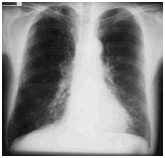

石綿(アスベスト)肺とは、肺線維症(じん肺)という病気の1つです。

肺が線維化(せんいか)することで、息切れや運動能力の低下が表れます。

石綿(アスベスト)肺の診断には、胸部X線検査とCT検査が用いられます。

肺の線維化は、粉じんや薬品でも起きる現象です。

そのため、石綿のばく露によっておきた肺線維症を「石綿(アスベスト)肺」とよんでいます。

画像引用元:3. 石綿肺 アスベスト(石綿)関連疾患 アスベスト(石綿)とは? 独立行政法人 環境再生保全機構